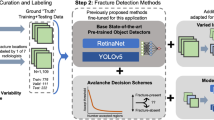

To collect data for constructing the CNN-based rib fracture detection model, the radiologists marked the fractures on the graphs. One radiologist marked the fracture sites on 1080 radiographs with the following signs: (1) complete rip disruption with a lucent line, (2) disruption of the inner or outer cortex, (3) fracture rib end displacement and (4) rib deformity with callus formation. To reduce the mark error, another radiologist confirmed all markers. As shown in Fig. 2, the training set contains 912 of the 1080 radiographs containing rib fractures, and the testing set contains 168 of the 1080 radiographs containing rib fractures and 233 radiographs not containing rib fractures. An additional validation set contains 201 chest radiographs collected from different period, 121 of which have rib fractures and 80 of which have not, and the validation set was confirmed by the same three radiologists with more than 15 years of radiological experience. One junior radiologist with 5 years of experience and one senior radiologist with 10 years of experience were also recruited for the rib fracture reading experiment.

Network training

YOLOv3 (https://pjreddie.com/darknet/yolo/) is a classic CNN algorithm with an excellent network structure (Fig. 5b). This model has several inherent advantages: fast evaluation, multiscale predictions, and a better backbone classifier. First, Darknet-53 was trained as the backbone for object detection. Darknet-53 (Fig. 5c) consists of 53 convolutional layers and one fully connected layer. Several consecutive 1 × 1 and 3 × 3 convolutions were added, and the first 52 layers were used to extract the image features. The k-means algorithm was used to count the size of the fracture marker in the labelled sample. To better detect the location of the fracture, each cell was responsible for predicting four anchors. One of these cells was selected as the prediction result, which used a total of 12 anchors: (54, 58), (61, 76), (65, 59), (69, 99), (74, 71), (80, 60), (85, 84), (94, 116), (104, 69), (111, 91), (122, 209) and (139, 123). Each box was classified using logistic regression analysis to determine whether the fracture area was included. After 50 iterations of network training, the losses of the training and testing sets were no longer reduced, indicating that the network converged to a stable state, as shown by the loss curve in Fig. 5d.